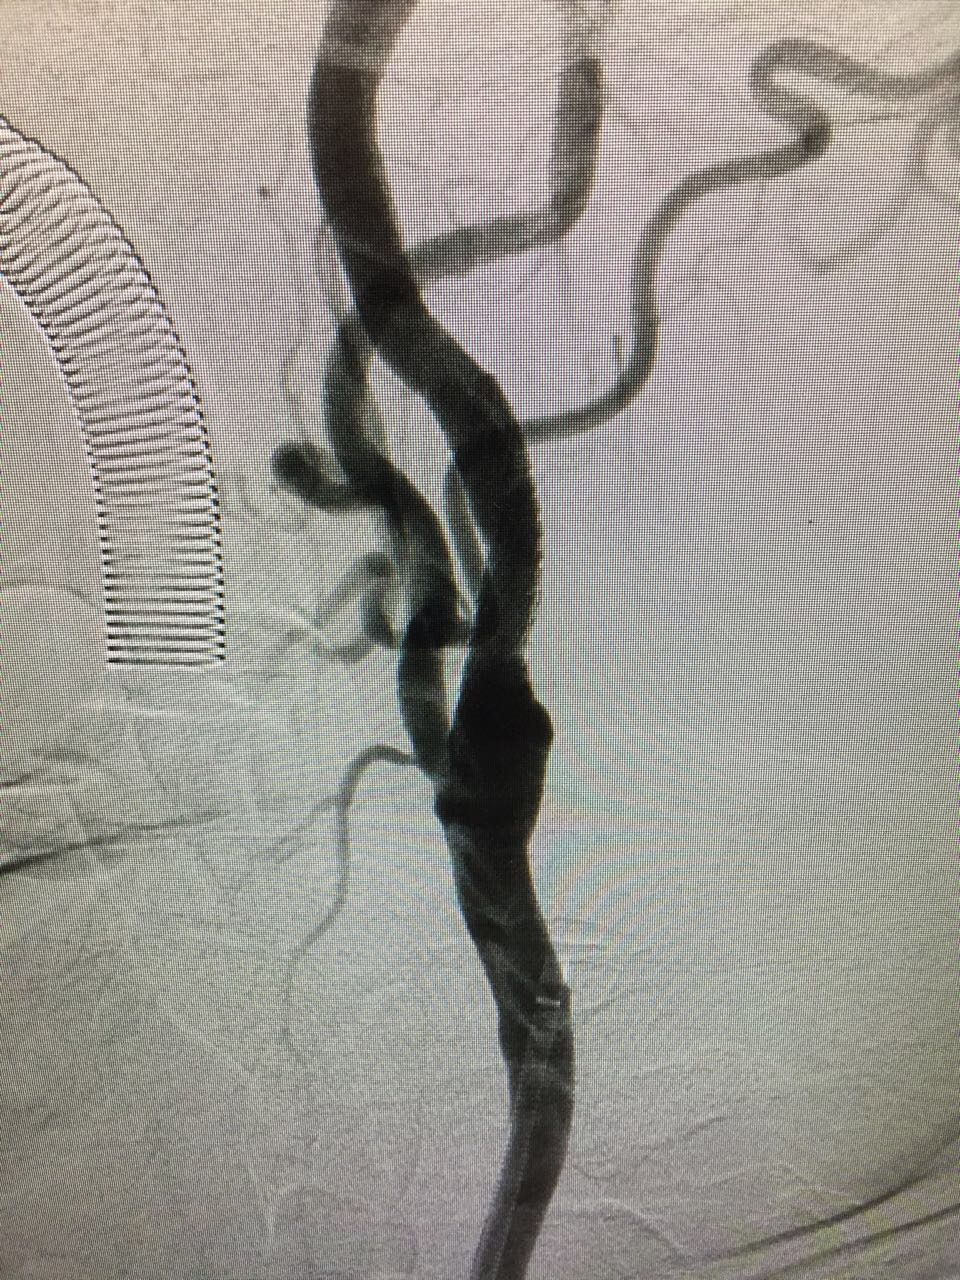

A frame image collection for your cases